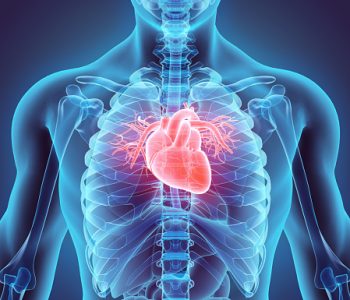

Infective endocarditis is an infection of the lining of the heart (endocardium) and often involves the valves of the heart as well as any areas with abnormal connections between the chambers of the heart or its blood vessels. It occurs when bacteria in the bloodstream clump on previously injured heart valves. Risk factors for endocarditis include injection drug use; compromised immune system; congenital heart defects; having a prosthetic (artificial) heart valve, pacemaker, or defibrillator; and deteriorated heart valves due to the aging process. Acute bacterial endocarditis usually begins suddenly with a high fever, tachycardia, and fatigue. Rapid and extensive heart valve damage occurs as a result.

Subacute bacterial endocarditis occurs gradually, causing symptoms like fatigue, low-grade fever, tachycardia, weight loss, diaphoresis, and anemia. Diagnostic tests for endocarditis include echocardiography to detect the damaged heart valves, a complete blood count, and blood cultures to identify the bacteria causing the infection. Treatments include high doses of antibiotics that are given intravenously, but sometimes surgery is needed to repair or replace damaged heart valves. Infective endocarditis affects twice as many men as women in all age groups. More than 25% of all cases occur in individuals over 60 years old.

Non-infective endocarditis occurs when blood clots that do not have bacterial contamination form on the heart valves and endocardium. It can progress to infective endocarditis if bacteria enter the bloodstream and attaches to the clots. In both infective and non-infective endocarditis blood clots can break free from the endocardium and heart valves, causing blockage of the arteries at major organs and stroke.